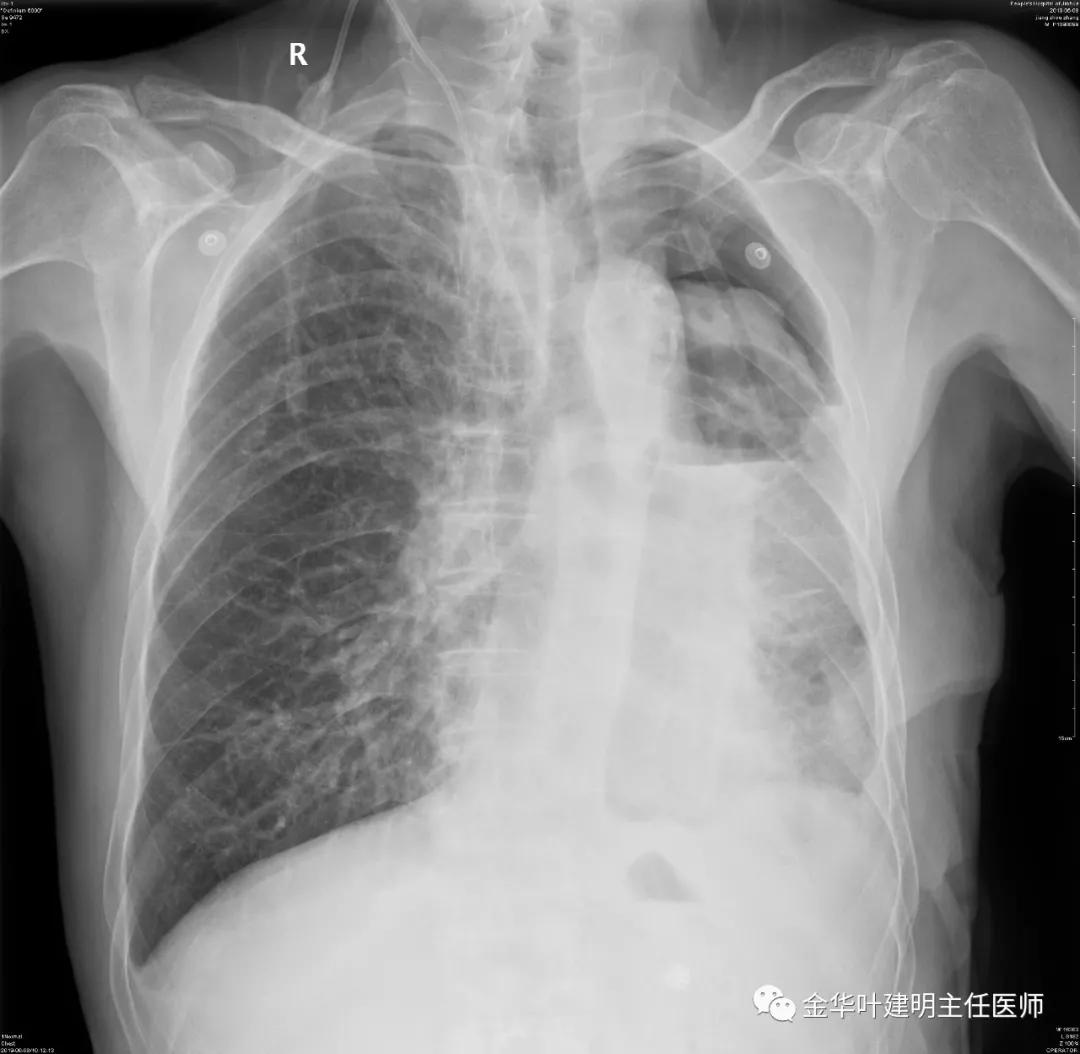

夹管情况下,于6.5复查胸片:

感觉左肺密度还可以,肺没有被全部压萎陷,积液有,但不是特别多。